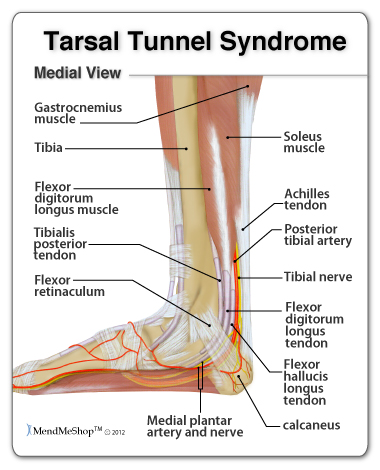

Tarsal Tunnel Syndrome

Running with Pain on the Inside of the Ankle Physiotherapy

Inside Ankle Pain Medial Symptoms Causes Treatment Rehab

Inside Ankle Pain Medial Symptoms Causes Treatment Rehab